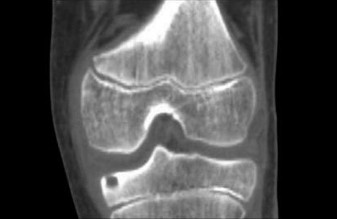

- Computed Tomography (CT) Scan: This is the gold standard for diagnosing and localizing osteoid osteomas. A high-resolution CT scan with thin axial and sagittal cuts is essential. It clearly delineates the central lucent nidus, the surrounding reactive sclerosis, and its precise relationship to cortical bone, medullary cavity, and vital adjacent structures (spinal canal, neural foramen, vessels). Reviewing these images in detail allows the surgeon to conceptualize the 3D anatomy and plan the safest and most direct surgical corridor.

- CT scan remains the cornerstone for diagnosis and precise localization of osteoid osteoma. Its ability to clearly visualize the central lucent nidus and surrounding reactive sclerosis is unparalleled, making it indispensable for surgical planning or guiding percutaneous procedures.